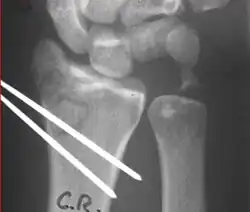

Surgery

Surgery is generally indicated for displaced or unstable fractures.[18] The techniques of surgical management include open reduction internal fixation (ORIF), external fixation, percutaneous pinning, or some combination of the above. The choice of operative treatment is often determined by the type of fracture, which can be categorized broadly into three groups: partial articular fractures, displaced articular fractures, and metaphyseal unstable extra- or minimal articular fractures.[5]

Surgical options have been shown to be successful in patients with unstable extra-articular or minimal articular distal radius fractures. These options include percutaneous pinning, external fixation, and ORIF using plating. Patients with low functional demand of their wrists can be treated successfully with nonsurgical management; however, in more active and fit patients with fractures that are reducible by closed means, nonbridging external fixation is preferred, as it has less serious complications when compared to other surgical options.[5] The most common complication associated with nonbridging external fixation is pin tract infection, which can be managed with antibiotics and frequent dressing changes, and rarely results in reoperation.[5] The external fixator is placed for 5 to 6 weeks and can be removed in an outpatient setting.[5]

Displaced intra-articular fractures

These fractures, although less common, often require surgery in active, healthy patients to address displacement of both the joint and the metaphysis. The two mainstays of treatment are bridging external fixation or ORIF. If reduction can be achieved by closed/percutaneous reduction, then open reduction can generally be avoided. Percutaneous pinning is preferred to plating due to similar clinical and radiological outcomes, as well as lower costs, when compared to plating, despite increased risk of superficial infections.[24] Level of joint restoration, as opposed to surgical technique, has been found to be a better indicator of functional outcomes.[5]